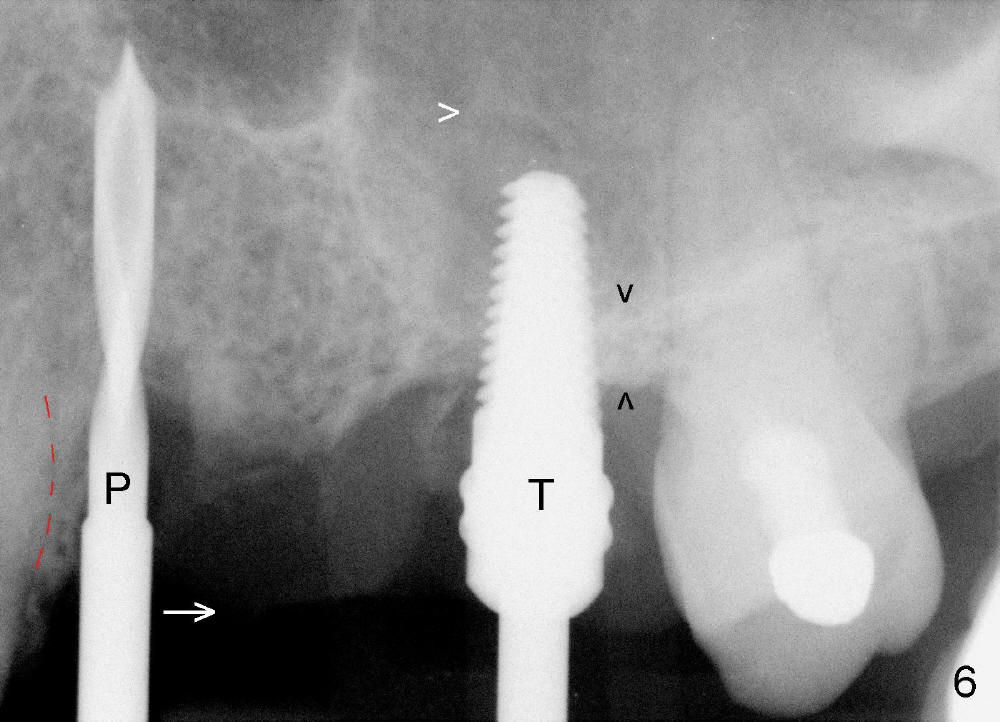

Initially the osteotomy is established with drill/reamers alternated with taps in the septum near the palatal socket. When a 4.5x14 mm tap (Fig.6 T; Fig.7: #14) is inserted, the sinus floor is perforated, but the sinus membrane is intact. When 7x14 mm tap is inserted, the sinus membrane is perforated in the buccal aspect of the osteotomy. The latter is repaired by placement of collagen dressing and then bone graft and membrane again (sandwich). The osteotomy is shifted to the palatal socket by using 5x14 and 6x14 mm taps. When the last tap is removed, the small area of the buccal aspect of the osteotomy is also found to be perforated, but the membrane is intact. When a 6x14 mm implant is placed (Fig.8), the coronal end is close to the middle of the socket (buccopalatally, due to angulation of the palatal socket).

Placement of immediate implant at the site of #12 is relatively easy. Adjustment is more or less mesiodistal. A 2 mm pilot drill (Fig.6 P) is found close to the root of the tooth #11 (red dashed line). The osteotomy is then moved distally (Fig.6 arrow). When 4.5x20 mm tap (Fig.7: #12) and 4.5x17 mm implant (Fig.8 I) are placed, there is distance from the root of the neighboring tooth. Insertion torque of the both implants is >60 Ncm. Abutments are placed (A in Fig.8) for immediate provisional.